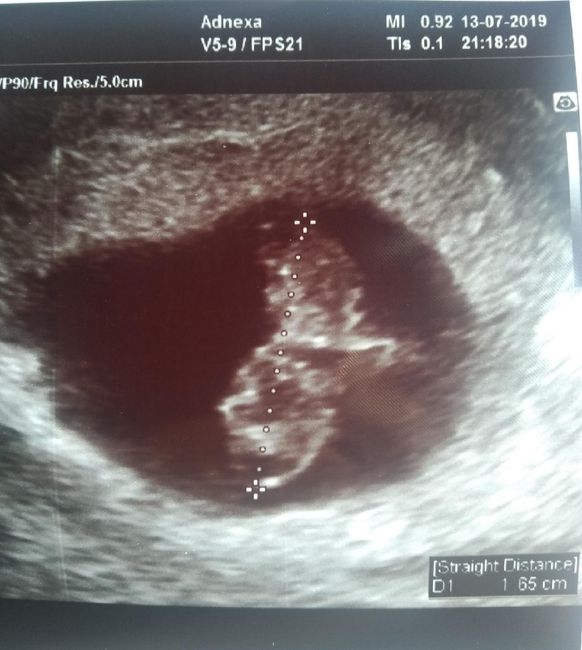

eco interna fatta a 8+2 secondo voi? Io vedo il cordone che va verso destra quindi presumo la placenta sia lì.... però non ho ancora capito sta teoriaScarica l'app

eco interna fatta a 8+2 secondo voi? Io vedo il cordone che va verso destra quindi presumo la placenta sia lì.... però non ho ancora capito sta teoria